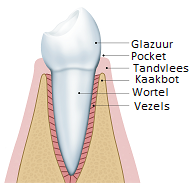

Gezond tandvlees

Gezond tandvlees is roze van kleur en ligt strak om de tanden en kiezen. Bovendien bloedt het tandvlees niet wanneer u eet of uw tanden poetst. Gezond tandvlees is de basis van een gezond gebit. Het tandvlees is samen met het kaakbot en de vezels het fundament van uw tanden en kiezen. Wie zijn tandvlees gezond houdt, kan jarenlang genieten van zijn eigen tanden en kiezen.